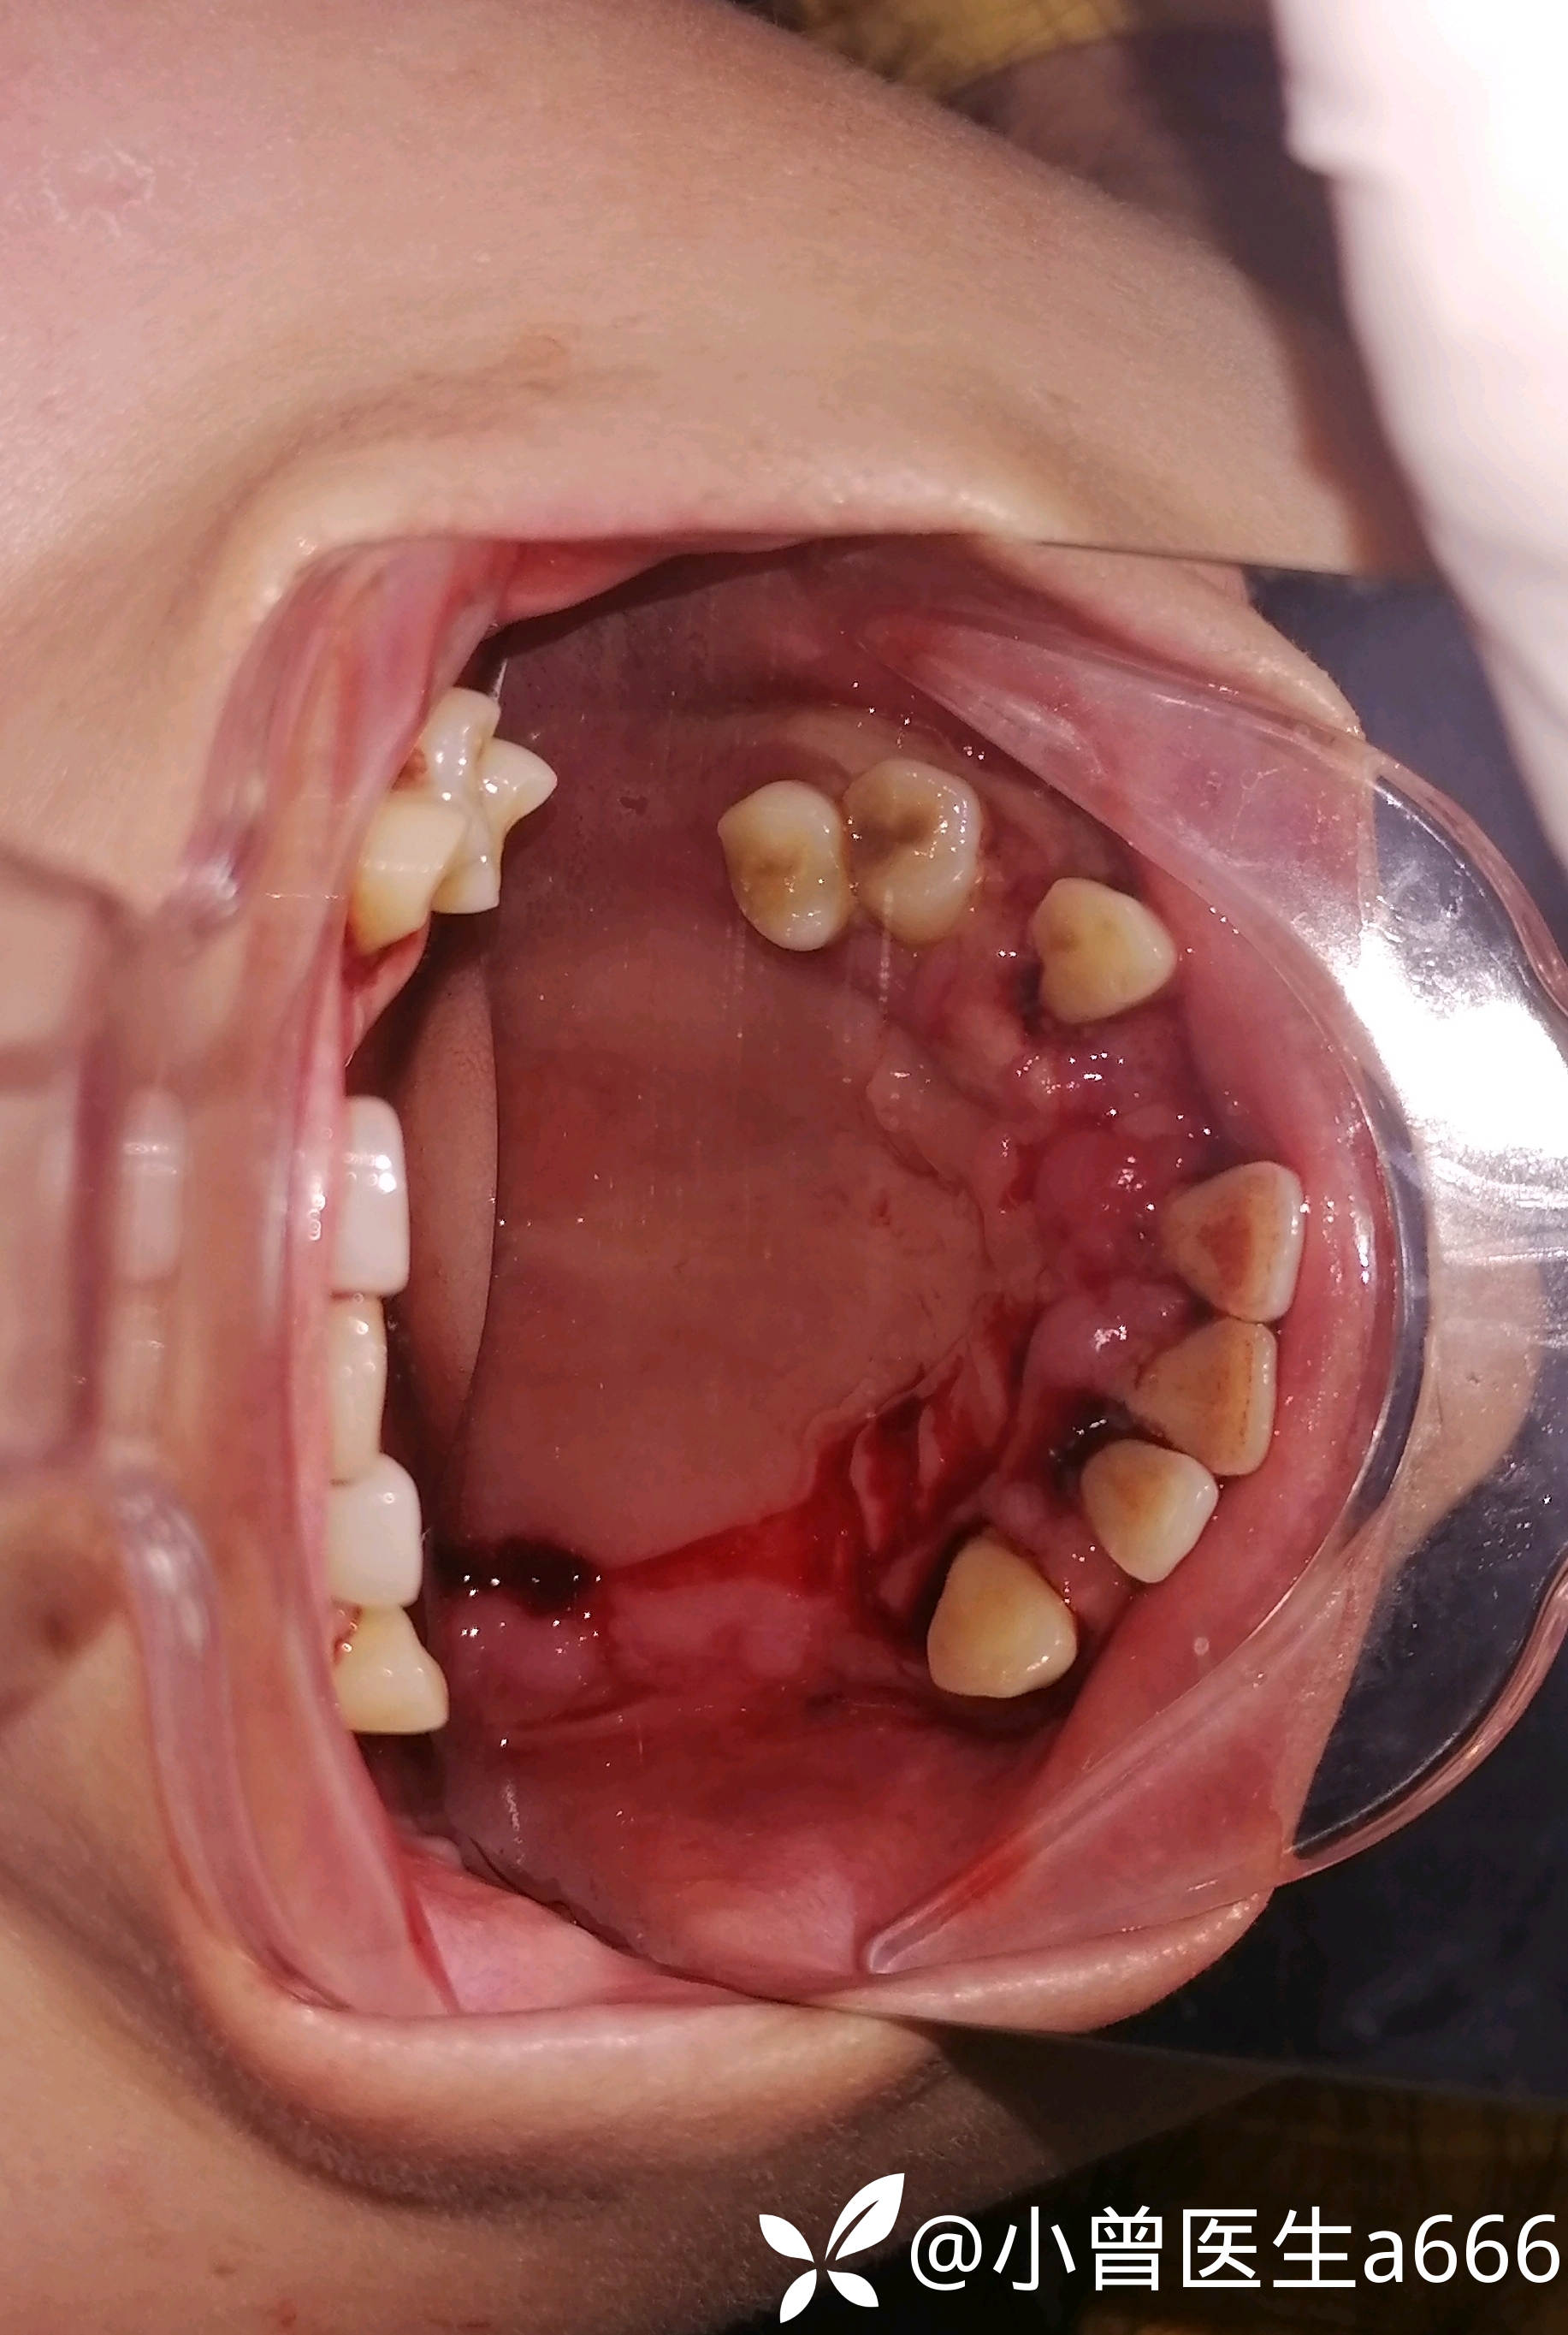

简要病史:患者自诉10年前发现刷牙出血情况,牙齿逐渐松动至脱落,只剩下口内这几颗牙了,剩下的牙都是松动三度的。4年前诊断出高血压,有服药史。

体格检查:全口牙龈红肿,探诊出血(+++),牙龈大面积溃疡溢脓,可探及深牙周袋,牙龈质软,牙龈退缩牙根暴露,见少量牙结石及软垢。牙龈牙齿检查未见疼痛不适。41缺失,41处牙龈肿胀增生至切1/3—1/2。视诊见下眼睑苍白无血色,皮肤暗黄,可见双臂皮肤斑点(患者自诉是过敏而致)